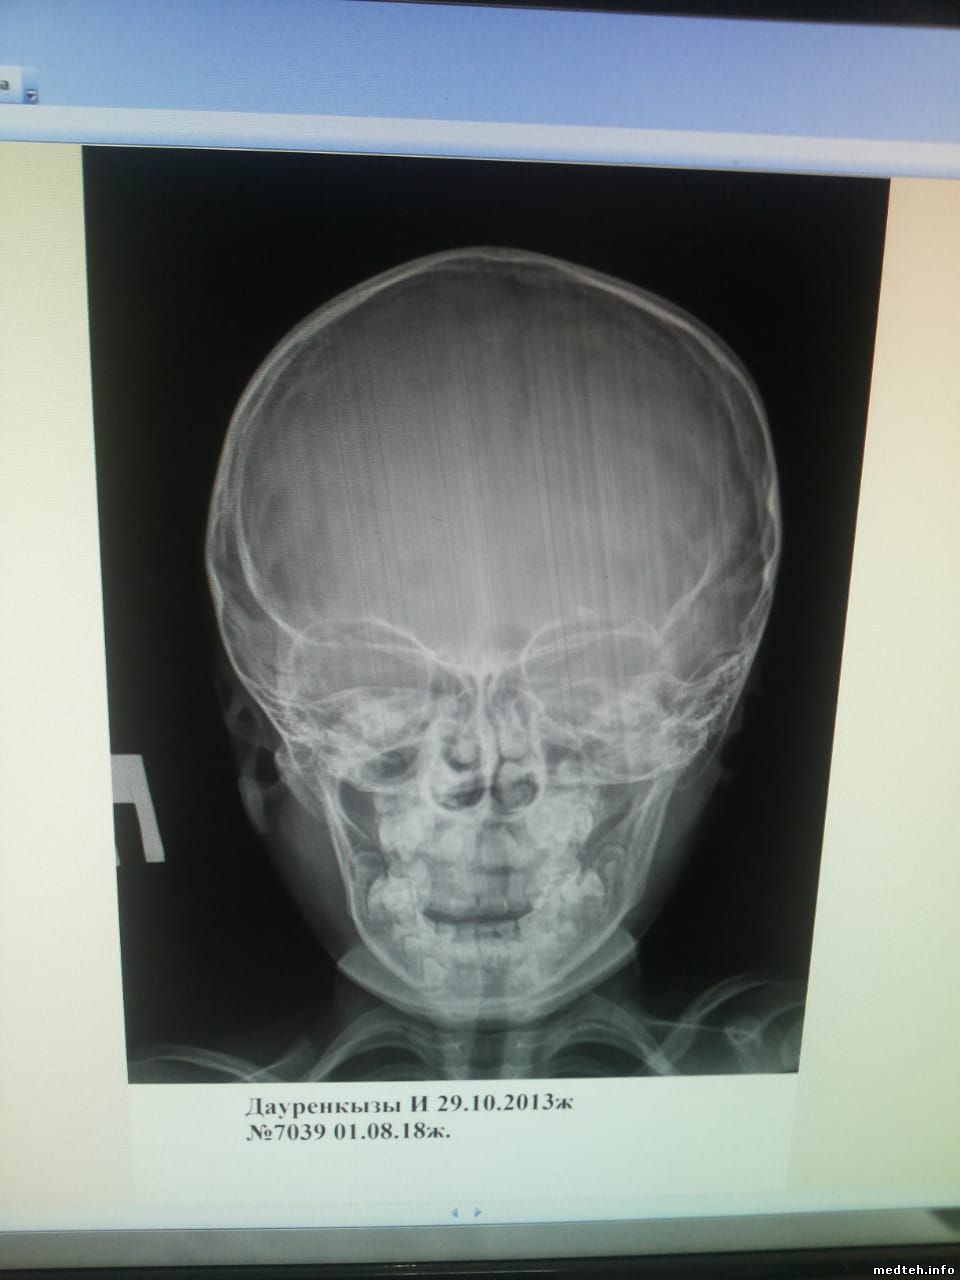

Здравствуйте дорогие форумчане, аппарат medonica blue-dr штатив потолочный, стойка детекторная, после хорошего скачка напряжения появились полосы на снимки, если раньше помогало полное выключение и перезагрузка то после последнего скачка напряжения полосы остались, ошибок никаких не показывает, сталкивался с похожей проблемой на филипсе помогла каллибровка трубки с детектором, но с данным аппаратом увиделся в первые мануал который имеется это строго описание работы и ошибки, кто сталкивался с данным аппаратом подскажите в чём может быть проблема, если в калибровке то как каллибровка делается на данном аппарате, за любую помощь буду очень благодарен фото прилагаю.